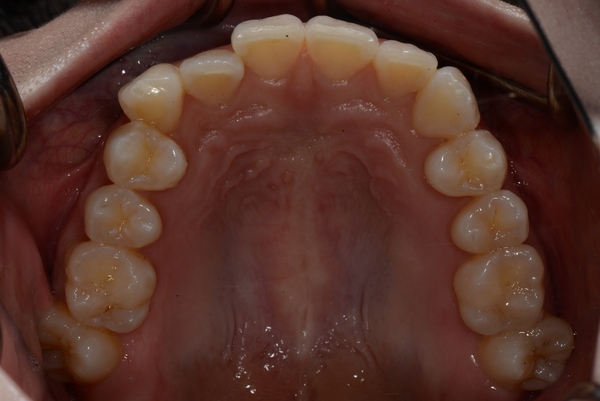

ガタガタとした歯並びや八重歯(叢生)CASE69